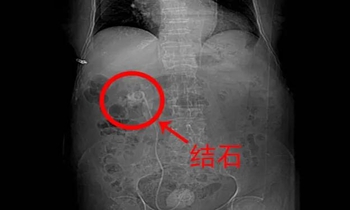

术后KUB